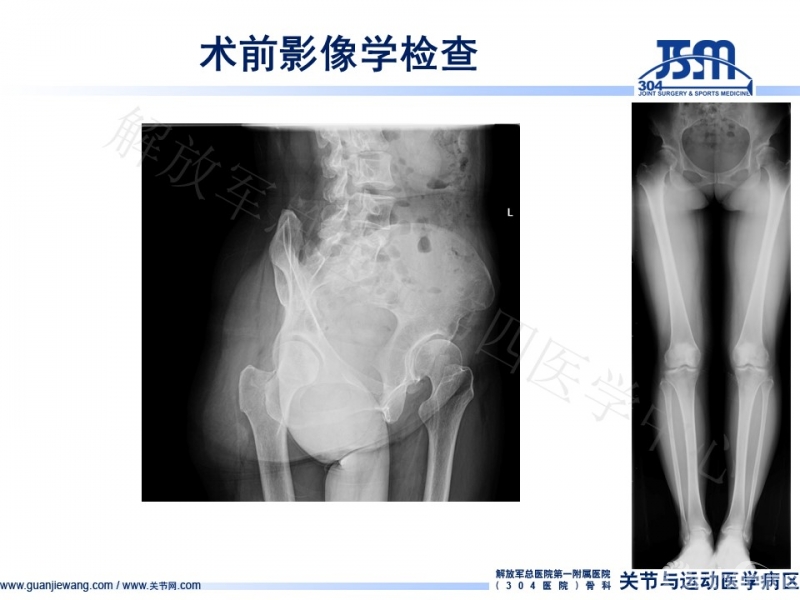

术前影像学检查